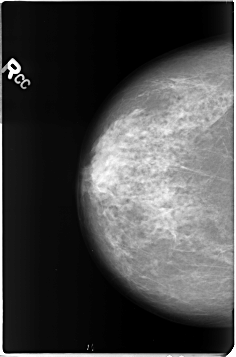

B_3361_1.RIGHT_CC

RIGHT_CC LINES 4632 PIXELS_PER_LINE 3064 BITS_PER_PIXEL 12 RESOLUTION 50 NON_OVERLAY